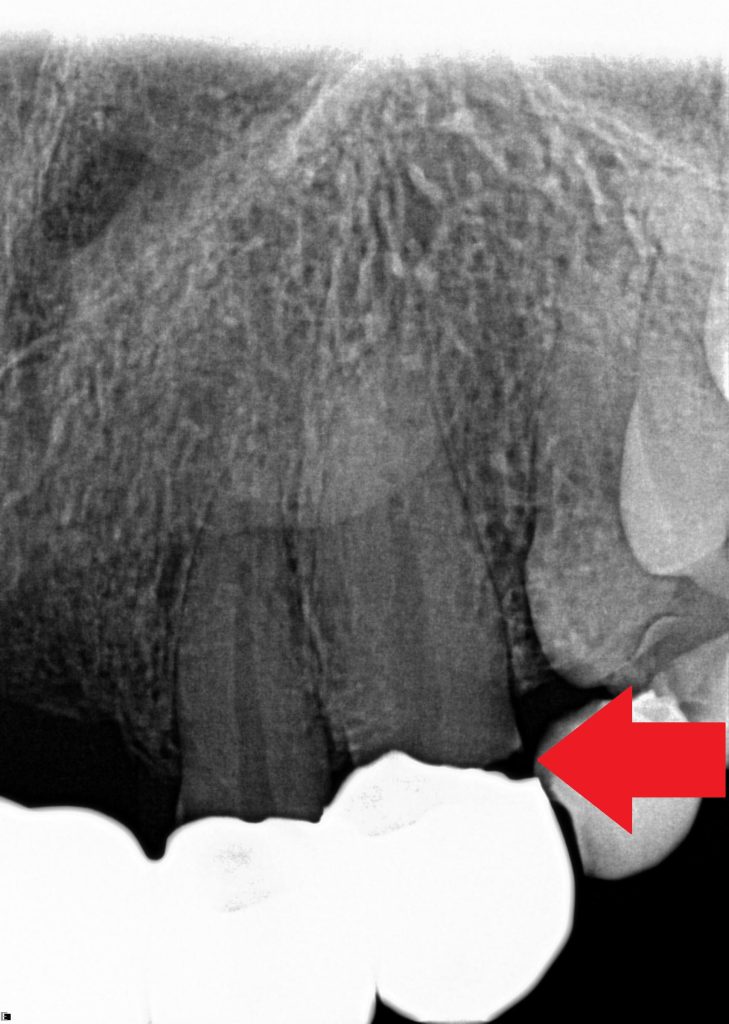

“I was completely shocked that this could happen, but more worrying was how the dentist didn’t notice, even after multiple X-rays.

Specialist solicitors at the Dental Law Partnership later revealed her dentist had provided completely unnecessary treatment – drilling healthy teeth, fitting a defective bridge, and ignoring months of agony.